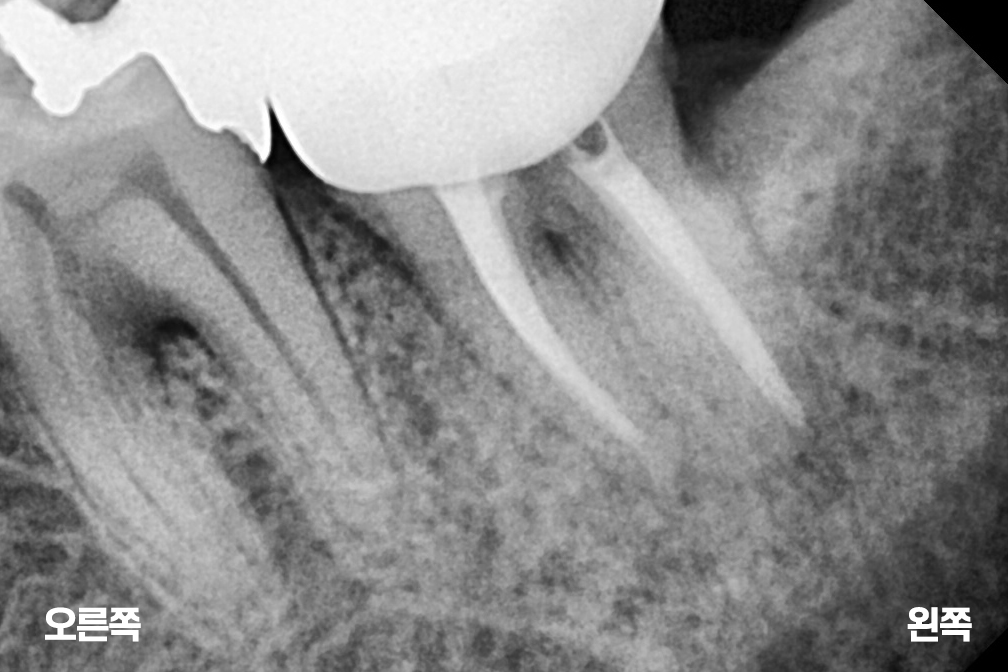

신경치료 아래쪽 어금니 재신경치료

재신경치료

Before 2025년 8월 16일

After 2026년 1월 20일